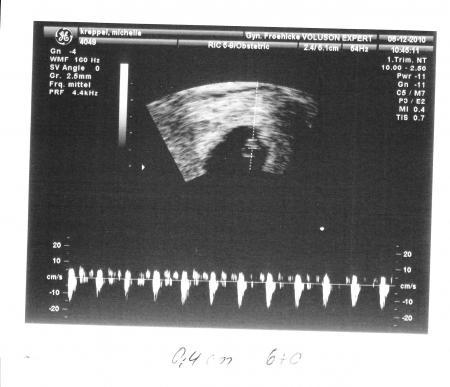

Das ist ja eine nette Idee!! Also ich habe am 12.Dezember positiv getestet und hatte dann meinen ersten FA-Termin am 23.Dezember! Da war ich dann in der 6.SSW und mein kleiner Mann war 0,48cm klein! Das Herzchen konnte ich da auch schon schlagen sehen! Glg, Claudia

Bild zu